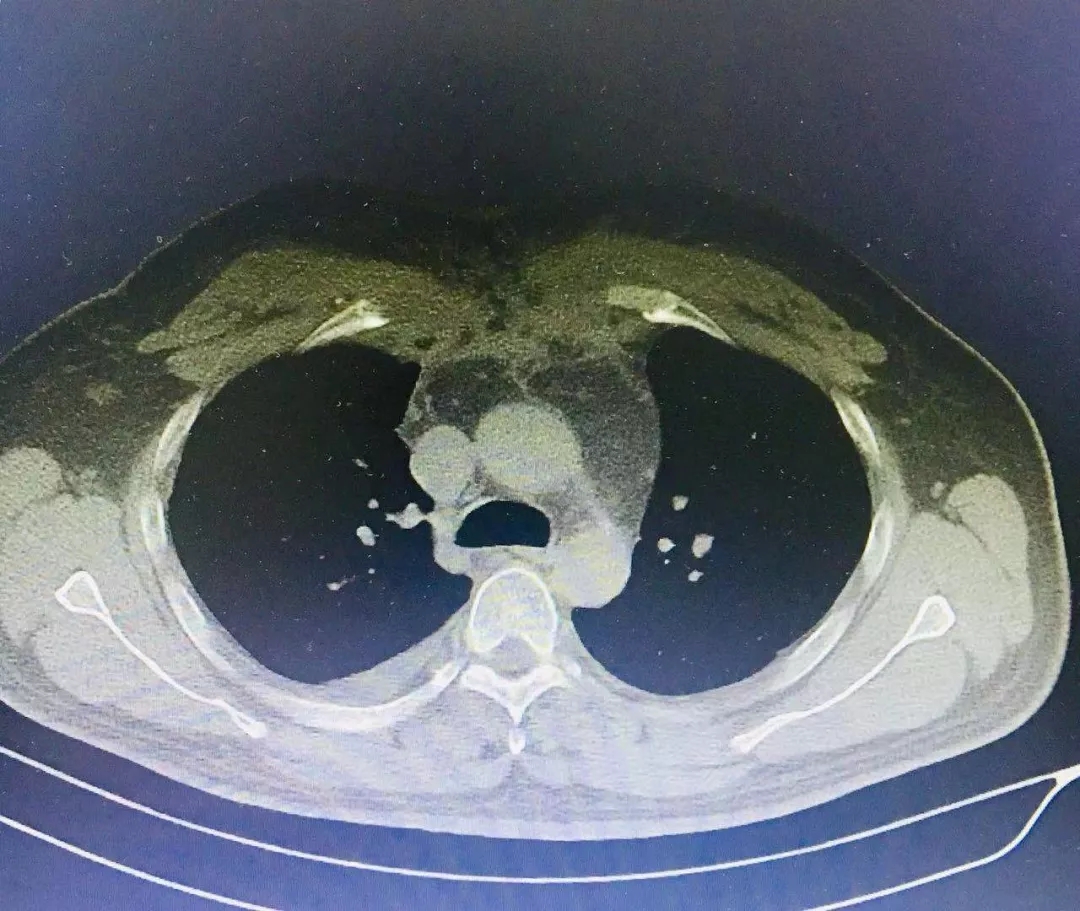

术后(图二)将病灶取而代之者是双侧丰厚的胸大肌

由于手术的难度之大,目前已经很少有人能够面对这种手术风险带来的压力了。然而,2019年7月23日,在我院胸外科、手术麻醉科的共同努力下,顽疾根治与胸壁重建手术的序幕拉开了:首先,作为主刀医生陈钢主任逐一切除了慢性病损的胸骨、双侧锁骨和双侧部分第一肋骨;手术扩创创面彻底清洗、消毒后,游离双侧胸大肌至锁骨中线区域,组织丰韵、血运优良的双侧胸大肌经过裁剪后向中拉拢,完美的覆盖在手术扩创后的创面上,经过四个多小时的精心雕琢,彻底扩创与胸壁重建的手术圆满结束。